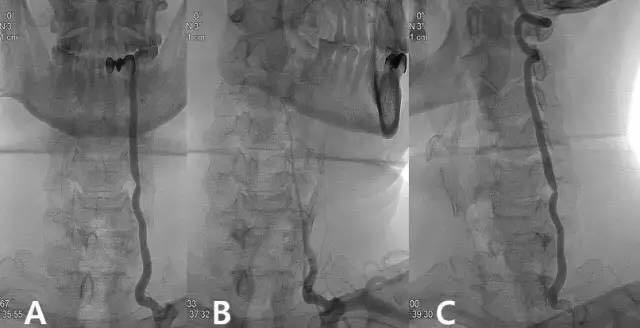

3.旋转椎动脉闭塞综合征(也称为Bow-Hunter's综合征、Powers's综合征)是一种非常少见(rare)疾病,因为已有神经内科单独命名,不应归结于椎动脉型颈椎病。

Powers's综合征,转头时椎动脉血流明显减少(图片来自文献)